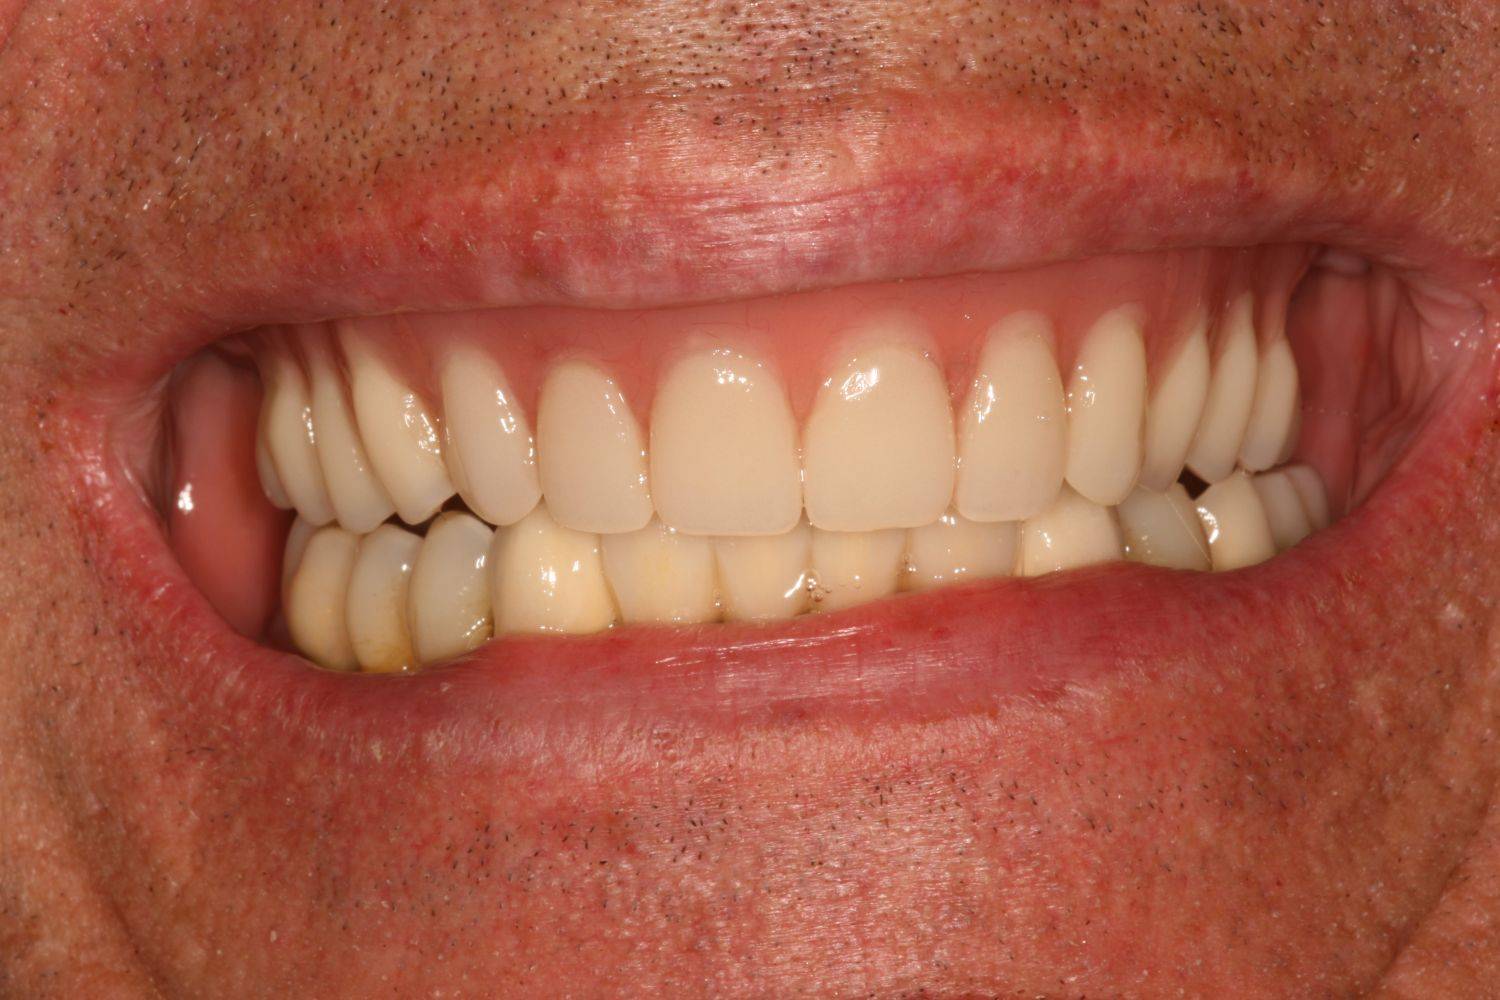

11. eset

27 éves páciensünk egész életében rettegett a fogorvosi beavatkozásoktól. Az összes foga elszuvasodott. A legkárosodottabb fogak gyökérkezelése és a szuvasodásainak megszűntetése után 26 fémkerámia koronát kapott a páciens. Erre a kezelésre is nagyon büszkék vagyunk. 2 hét leforgása alatt sikerült jelentős mértékben javítanunk a páciensünk mosolyán, önbizalmán és mióta velünk talalákozott, már a fogászati kezelésektől sem fél annyira!